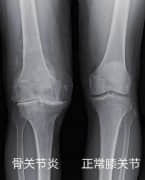

关节疼痛是怎么回事?骨关节炎是什么原因引起的?

膝关节骨性关节炎的部分症状和原因

骨刺还是骨关节炎?这个是值得思考的问题